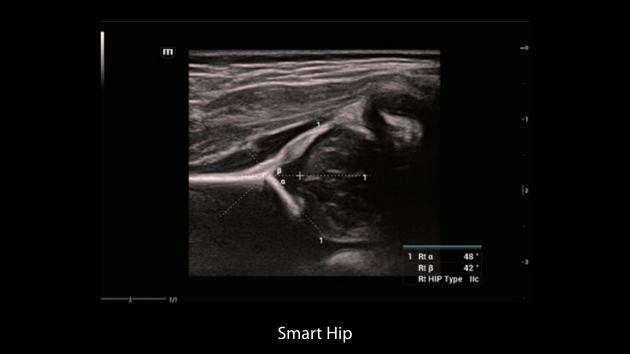

Le Nuewa?I9, con?u spÃĐcialement pour la santÃĐ de la femme et les soins nÃĐonataux, offre une expÃĐrience entiÃĻrement nouvelle gr?ce aux innovations dont il est dotÃĐ, tant à lâintÃĐrieur quâà lâextÃĐrieur. Ces innovations sont dÃĐveloppÃĐes sur la base d'une comprÃĐhension approfondie de scÃĐnarios cliniques complexes, fournissant des rÃĐponses prÃĐcises et adaptÃĐes ainsi qu'une efficacitÃĐ exceptionnelle et une expÃĐrience utilisateur remarquable.

La plate-forme ZST+?est une innovation extraordinaire, reprÃĐsentant une ÃĐvolution de lâimagerie ultrasonore. Elle transforme la formation conventionnelle de faisceaux en un traitement basÃĐ sur les canaux de donnÃĐes. Elle repousse les limites de lâimagerie conventionnelle et du compromis entre rÃĐsolution spatiale, rÃĐsolution temporelle et uniformitÃĐ tissulaire en offrant une qualitÃĐ dâimage exceptionnelle pour des solutions dâimagerie infinies et en constante ÃĐvolution.